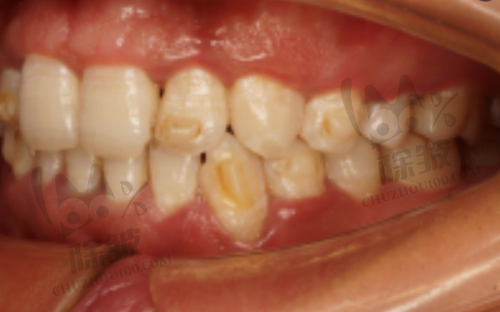

西安袁林天儿童口腔医院是由原第四口腔医院医学博士、儿童口腔医学骨干医生袁林天创办的,也是西北地区初家儿童口腔专精医院。这家医院专注为国内家庭提供高质量的口腔医疗服务,尤其致力于为儿童提供全方面专精的口腔诊疗保健服务。医院的骨干医生团队实力雄厚,由专精的儿童口腔医生坐诊,他们经验多,能根据孩子的不同情况制定个性化的治疗方案。在收费方面,虽然具体价格会因治疗项目而异,但总体来说性价比还是比较高的。不少家长反馈,在这里给孩子看牙,医生耐心细致,孩子也比较配合。有位家长带孩子来看龋齿,医生不仅治疗得特别专精,还耐心地给孩子讲解口腔卫生知识,让孩子从小就养成良好的口腔习惯。

儿童口腔门诊是专门接诊12岁以下儿童的专精门诊。门诊配备了10台牙椅,9间独立诊室,1间手术室,1间放射室,还配置了专门的清洗消毒室及儿童游乐室。整个诊疗区都进行了儿童风格的装修和布置,一进入诊区,孩子就会产生浓厚的兴趣,大大减轻了儿童看牙的恐惧。同时,每个诊室都配置了镇静装置、全麻呼吸机,针对一些无法配合的儿童也能顺利完成口腔舒适化治疗,提升就诊体验。收费方面,儿童牙科检查费用在100元至300元之间,相对比较合理。有家长说,以前带孩子看牙,孩子总是哭闹不肯配合,自从来到这家门诊,孩子看到可爱的装修和好玩的游乐室,看牙变得轻松多了。

西安中诺口腔是连锁口腔,院内的硬件设施和技术都特别不错。院长做成人口腔种植矫正特别有名,做儿牙也相当出色,有专门的儿童牙医亲诊。这些儿童牙医会对孩子的口腔问题进行全方面检查诊疗,以便及时发现和干预儿童牙齿出现的问题。医院的技术口碑都特别不错,值得家长们信赖。在收费上,韩国美格真种植牙特价3890元起一颗。有个孩子牙齿不齐,在西安中诺口腔医院进行矫正,医生根据孩子的牙齿情况制定了详细的矫正方案,经过一段时间的治疗,孩子的牙齿变得整齐了,家长对治疗成效非常满意。

西安海涛口腔医院是一家连锁口腔,在西安本地拥有多家分院。在儿童牙齿方面,医院提出了针对儿童牙齿的预防方案,对于孩子的龋齿治疗、地包天MRC干预等具有特别不错的治疗改善成效。医院起源于1950年的长安牙医馆,历史悠久。其水激光种植疼痛感轻微,出血少,“1日得”种植牙也非常受欢迎,当天就可修复全口牙齿的咀嚼力。收费方面,韩国DTS进口种植牙3888元起,青少年金属托槽矫正5888元起。有家长带孩子来治疗龋齿,医生采用精良的治疗方法,孩子治疗过程中没有感觉到太多痛苦,而且治疗后修复得也特别快。

西安诺贝尔口腔是一家连锁口腔品牌,对于各种口腔牙齿问题的治疗改善都特别不错。在儿童牙齿治疗方面,院内的技术口碑都挺好的,对于常见的儿牙龋齿、儿牙拔除、儿牙根管治疗等都能得到合理有效的改善,特别多宝妈们对诺贝尔口腔的技术评价都是好评。医院邀请了来自四 医 大、西安交通大学的口腔医生,还会定期邀请北京、广州、上海的硕博导师医生前来坐诊。收费上,iti植体优惠价9900元起。有个孩子需要拔除乳牙,在西安诺贝尔口腔,医生操作熟练,孩子没有感到太多疼痛,术后修复也特别顺利。

西安小白兔口腔早在2003年就成立了,光是在雁塔区就有10家左右的分院,开展200多个精细的口腔项目,也是一家无假日口腔医院。费用非常亲民,儿牙、早期矫正非常有名。医院杜绝“把孩子恐吓到牙椅上”,特别擅长和孩子沟通,治疗手法轻柔。儿童全口涂氟59元起,青少年金属矫正10960元起。医院有专门的儿童牙椅和儿童玩耍区,可以在看牙时降低孩子的恐惧感。有家长带孩子来做早期矫正,孩子一开始特别害怕,但是在医生的耐心引导和舒适的环境下,孩子逐渐放松下来,配合治疗。经过一段时间的矫正,孩子的牙齿有了明显的改善。

美奥口腔在西安共有5家分院,南郊北郊东郊西郊的牙友们看牙都不用跑远路。医院有专门的儿童MRC早期矫治培训医师,光是专门给小朋友们矫正的医生就有10几位,像四 医 大从业20多年的冯雪医生还有四 医 大博士马振国,都在美奥口腔。再加上有专门的儿牙诊室和儿童活动中 心,孩子正畸就像玩一样,不会有哭闹的情绪,每个分院还有粉红诊室,牙椅、窗帘、抱枕什么的都是粉色的,女孩子们尤其喜欢。早期MRC肌功能矫治4000元起、青少年金属矫正6800元起。有个小女孩牙齿不齐,在美奥口腔进行矫正,在舒适的环境和专精医生的指导下,孩子积极配合治疗,现在牙齿已经变得整齐美观了。

西安瑞泰口腔在雁塔区共有4家分院,成立也已经有10几年了。医院有专门的宝宝牙齿矫正宣教室,用通俗易懂的语言让宝宝明白牙齿矫正的重要性,从而更加配合,不会有反抗心理,医生也有进行过专门的儿童心理学研修。暑假期间,孩子矫正还会有好多优惠活动。金属自锁托槽9999元起、时代天使儿童隐形矫正20000元起。医院做儿牙用的是全麻,并且有具备资质的麻醉医生。有个孩子比较害怕看牙,在瑞泰口腔,医生通过耐心的沟通和专精的引导,让孩子逐渐接受治疗,并且在全麻下顺利完成了矫正手术,术后修复得也良好。

西安团圆口腔是一家规模超大的二级口腔医院,共有8层楼,有好多四 医 大、北大口腔返聘回来的医生。医院有专门的儿童游乐场,孩子可以在里面玩摇摇木马、滑滑梯等。他家的儿童牙齿矫正主要接诊的是8岁以上的孩子,仪器设备比较齐全,拥有超大数字化3D检查中 心,可以让家长提前看到宝宝做完正畸后的样子,各个时期也有优惠。儿童早期MRC肌功能矫治3500元起、金属自锁托槽矫正9800元起,时代天使隐形矫正儿童版18000元起。有家长带孩子来做矫正,通过3D检查中 心提前看到了矫正后的成效,心里更有底了,孩子在舒适的环境下也特别配合治疗,现在牙齿矫正成效正在逐渐显现。

西安赛德阳光口腔是一家主做矫正的连锁口腔机构,是由北大口腔博导周彦恒医生创建的,自2007年成立以来就比较受欢迎,目前积累的矫正实例已经有16万例。针对于儿童矫正,不反弹,舒适无疼,能塑造出好看的脸型。青少年金属矫正1.5万元起。有位家长带孩子来做矫正,医生根据孩子的牙齿情况制定了科学的矫正方案,孩子在治疗过程中没有感觉到太多痛苦,而且随着治疗的进行,脸型也变得更加美观了,家长对治疗成效非常满意。